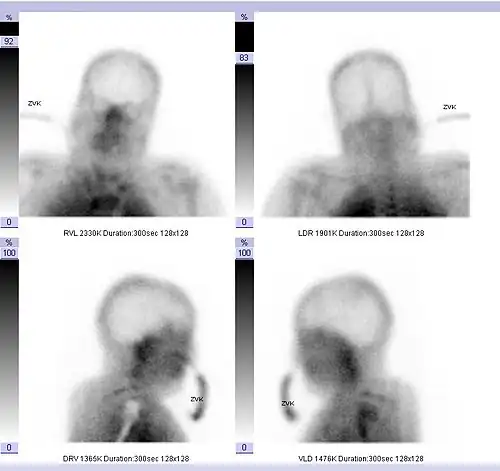

- Ein mittels zerebraler Hirnperfusionsszintigraphie oder Doppler-Sonographie festgestellter Durchblutungsstopp in allen hirnversorgenden Gefäßen. Bei der Perfusionsszintigraphie wird eine schwach radioaktiv markierte Substanz injiziert und ihre Verteilung im Gehirn verfolgt. Bei intakter Hirndurchblutung lässt sich die Markierungssubstanz über Stunden in den durchbluteten Hirnregionen nachweisen. Bei einem Hirntoten hingegen stellt sich die Schädelhöhle infolge eines Abbruchs der gesamten Hirndurchblutung „leer“ dar. Bei der Dopplersonographie werden die Hirnbasisarterien beschallt. Anhand der Reflexion des Schallsignals wird die Blutflussgeschwindigkeit in den Hirngefäßen gemessen. Die Dopplersonographie darf nur von einem hierin erfahrenen Untersucher vorgenommen werden und muss mindestens zweimal im Abstand von wenigstens 30 Minuten erfolgen.